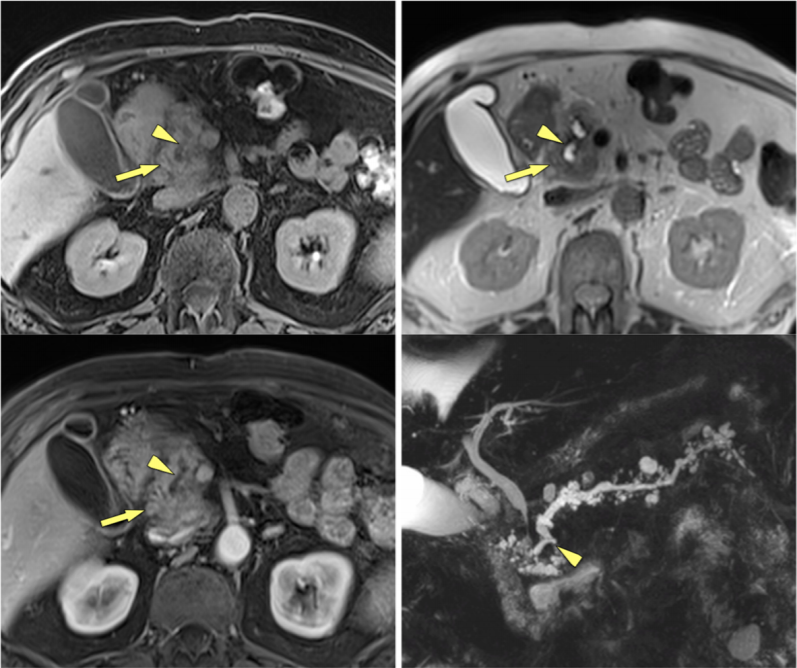

男性,86 岁,肿块型胰腺炎。胰头区见类肿物样异常信号(黄箭),其内可见胰管穿过(箭头),并且可见到多发分支胰管扩张(第四幅图,MRCP)。